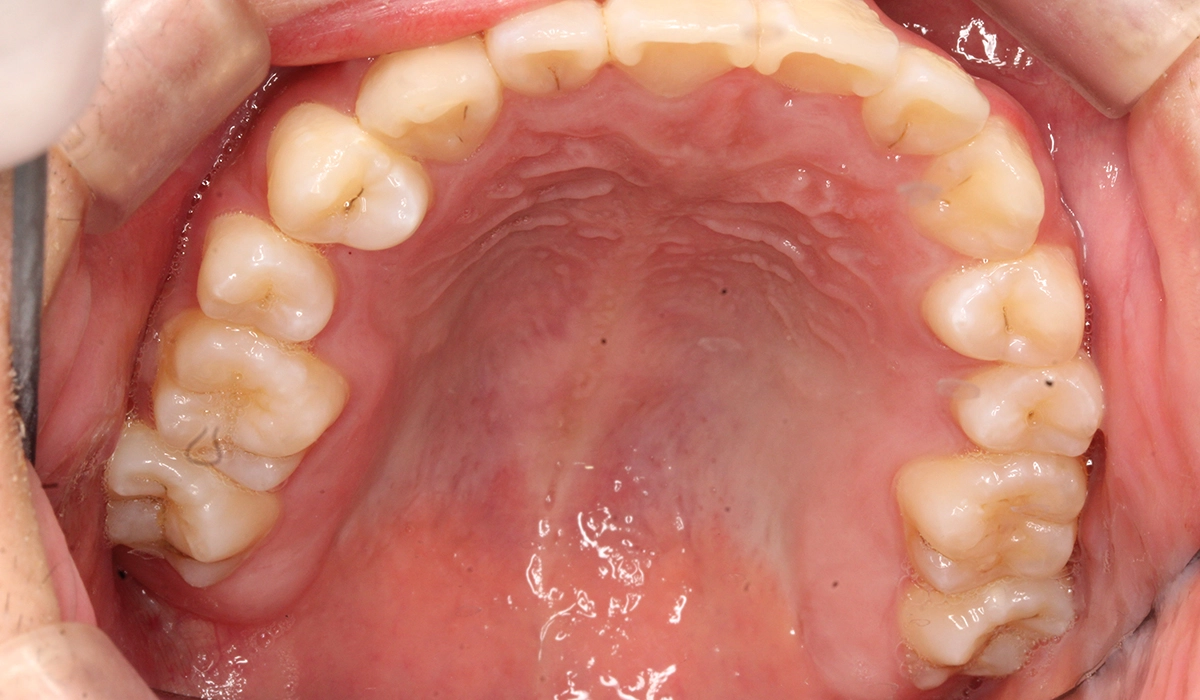

術前:上顎